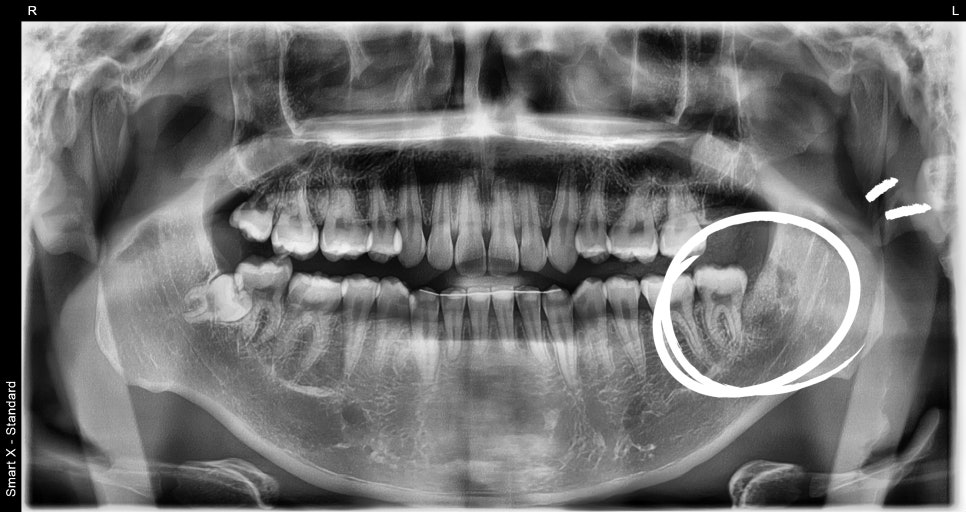

As a result of panoramic and small X-ray imaging,

an over 6 mm radiolucent lesion (dark-appearing cystic tissue) beneath the left mandibular third molar was identified,

and a tooth cyst was suspected.

Consistent with dentigerous cyst with abscess formation.

→ Considered a cystic lesion accompanied by abscess formation (tooth cyst, dentigerous cyst).

Dentigerous cyst (tooth cyst): A cyst that forms around an unerupted tooth. It is generally asymptomatic, but as it grows, it can cause pain or swelling.

Abscess formation: A condition in which an inflammatory lesion containing pus is present.